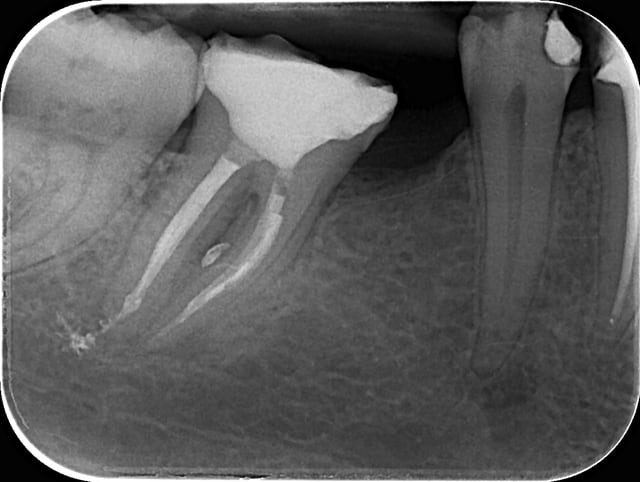

Apres obturation - fig.3,4